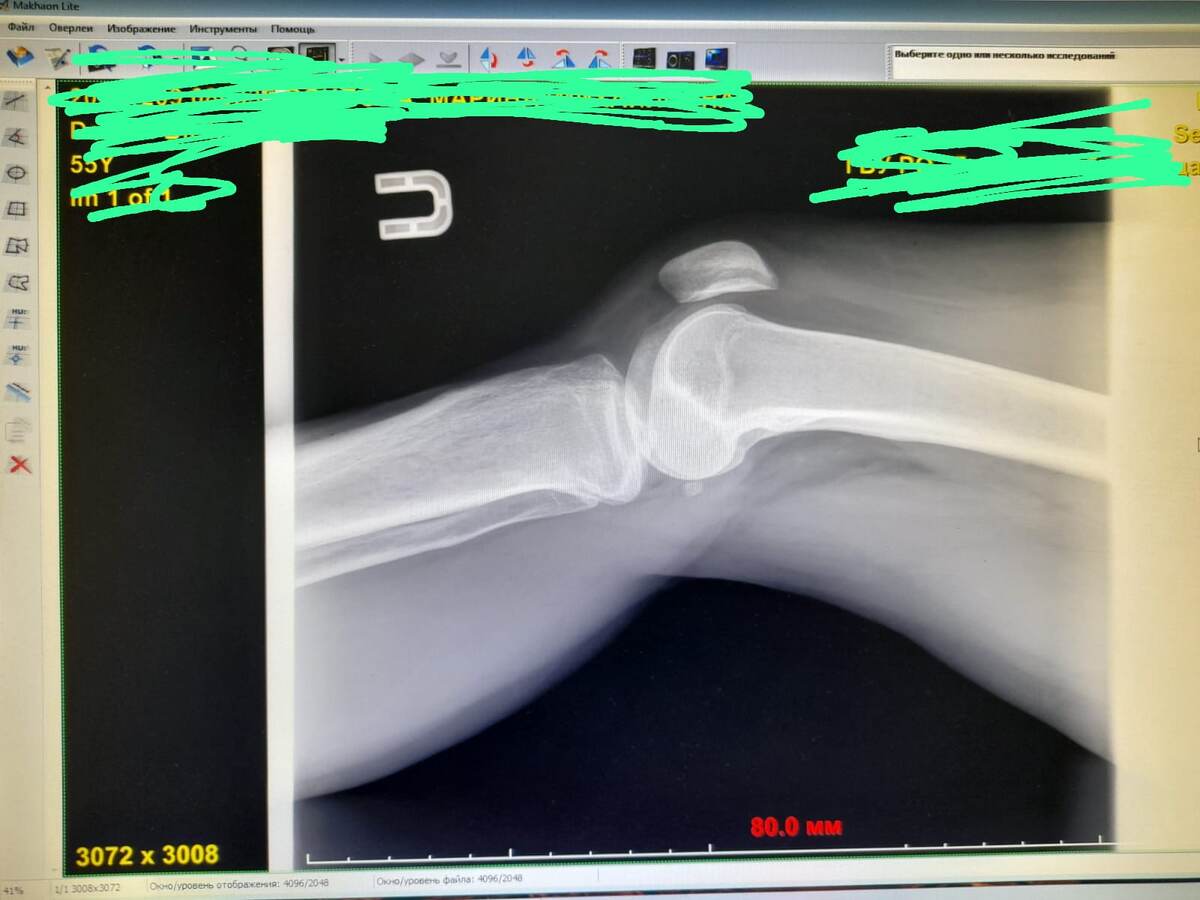

рентген в первый день начала воспаления (после ушиба)